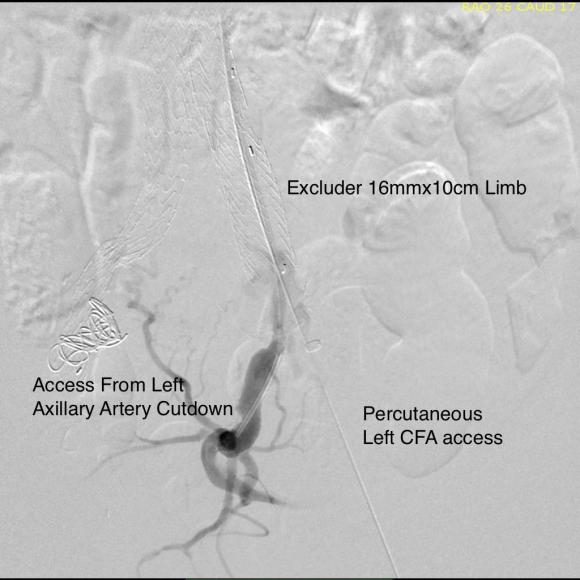

For example, take this patient who after EVAR of aortic aneurysm with AFX developed metachronous dilatation of the common iliac artery to 3.9cm with abdominal pain. The average diameter is 18.5mm. From the table, that rounds to 19mm corresponding to 283.53 square mm. If the internal iliac artery requires a 13mm graft, that is 132.73 square mm, the difference being 150.80 square mm. That corresponds to a 14mm diameter graft, but a slightly larger graft is preferred for oversizing. The external iliac artery is 8mm, and putting a 13mm Viabahn (largest available) in that would result in the B-infolding in the 8mm external iliac. Here, I bailed myself out by simply placing a 20mm AFX iliac limb extension, which by virtue of its design is resistent to infolding and tolerant of parallel grafts laid alongside in constricted channels. I found that the AFX iliac limb, a 20-13mm x 88mm length extension well suited for this.

The AFX graft limb seems to adapt to the presence of the parallel “sandwich” graft which is deployed second and ballooned last. In followup, there was shrinkage of the common iliac artery aneurysm sac and no endoleak.

Compared to my other parallel graft case treating a metachronous saccular common iliac aneurysm years after an EVAR with a Gore endograft (link), which by table calculation, resulted in 8% oversize in calculated areas, this particular technique with a large AFX graft and an appropriately sized Viabahn seemed to work well the setting of a previously placed AFX graft. It allows one to avoid hypogastric occlusion.